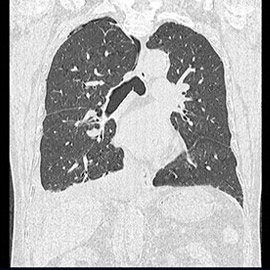

80列マルチスライスCT 検査 画像例

80列マルチスライスCTで撮影した画像

胸部